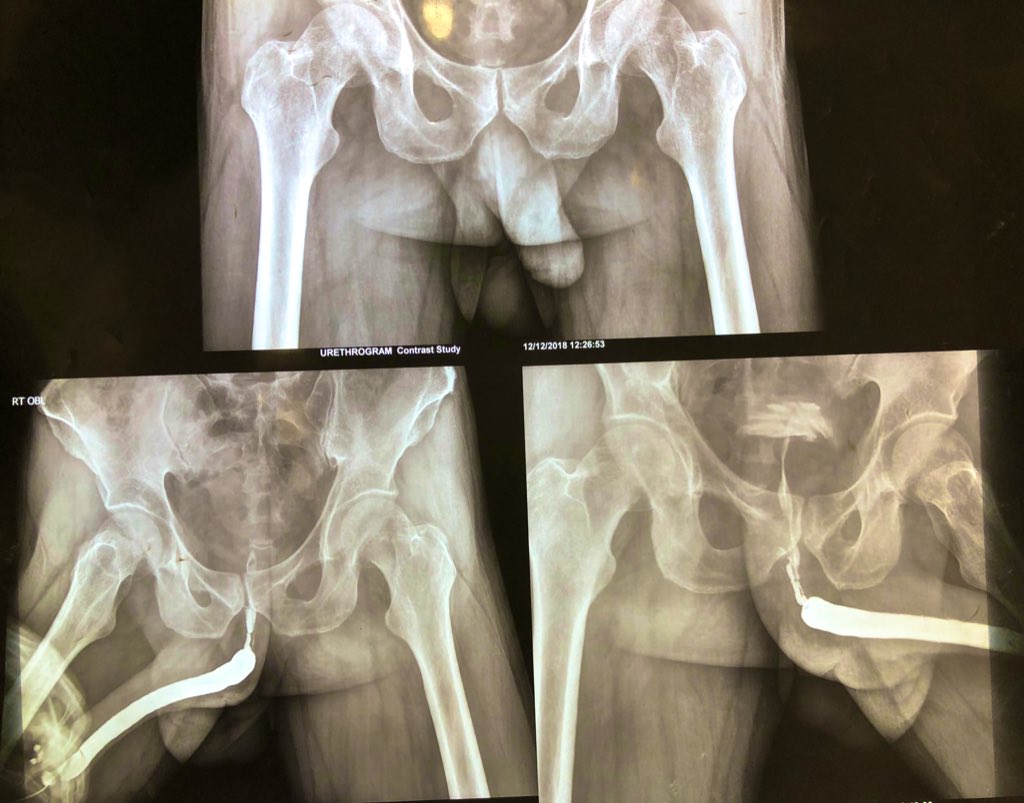

One of the first #PFUDD I did when first moved to HK few years ago. 😊 wonder out there how and how long are they followed up?

@vturodynamic @drjoshi_pankaj @sanjaybkulkarni @DrJustinChee @DrDevangDesai @MajShabbir